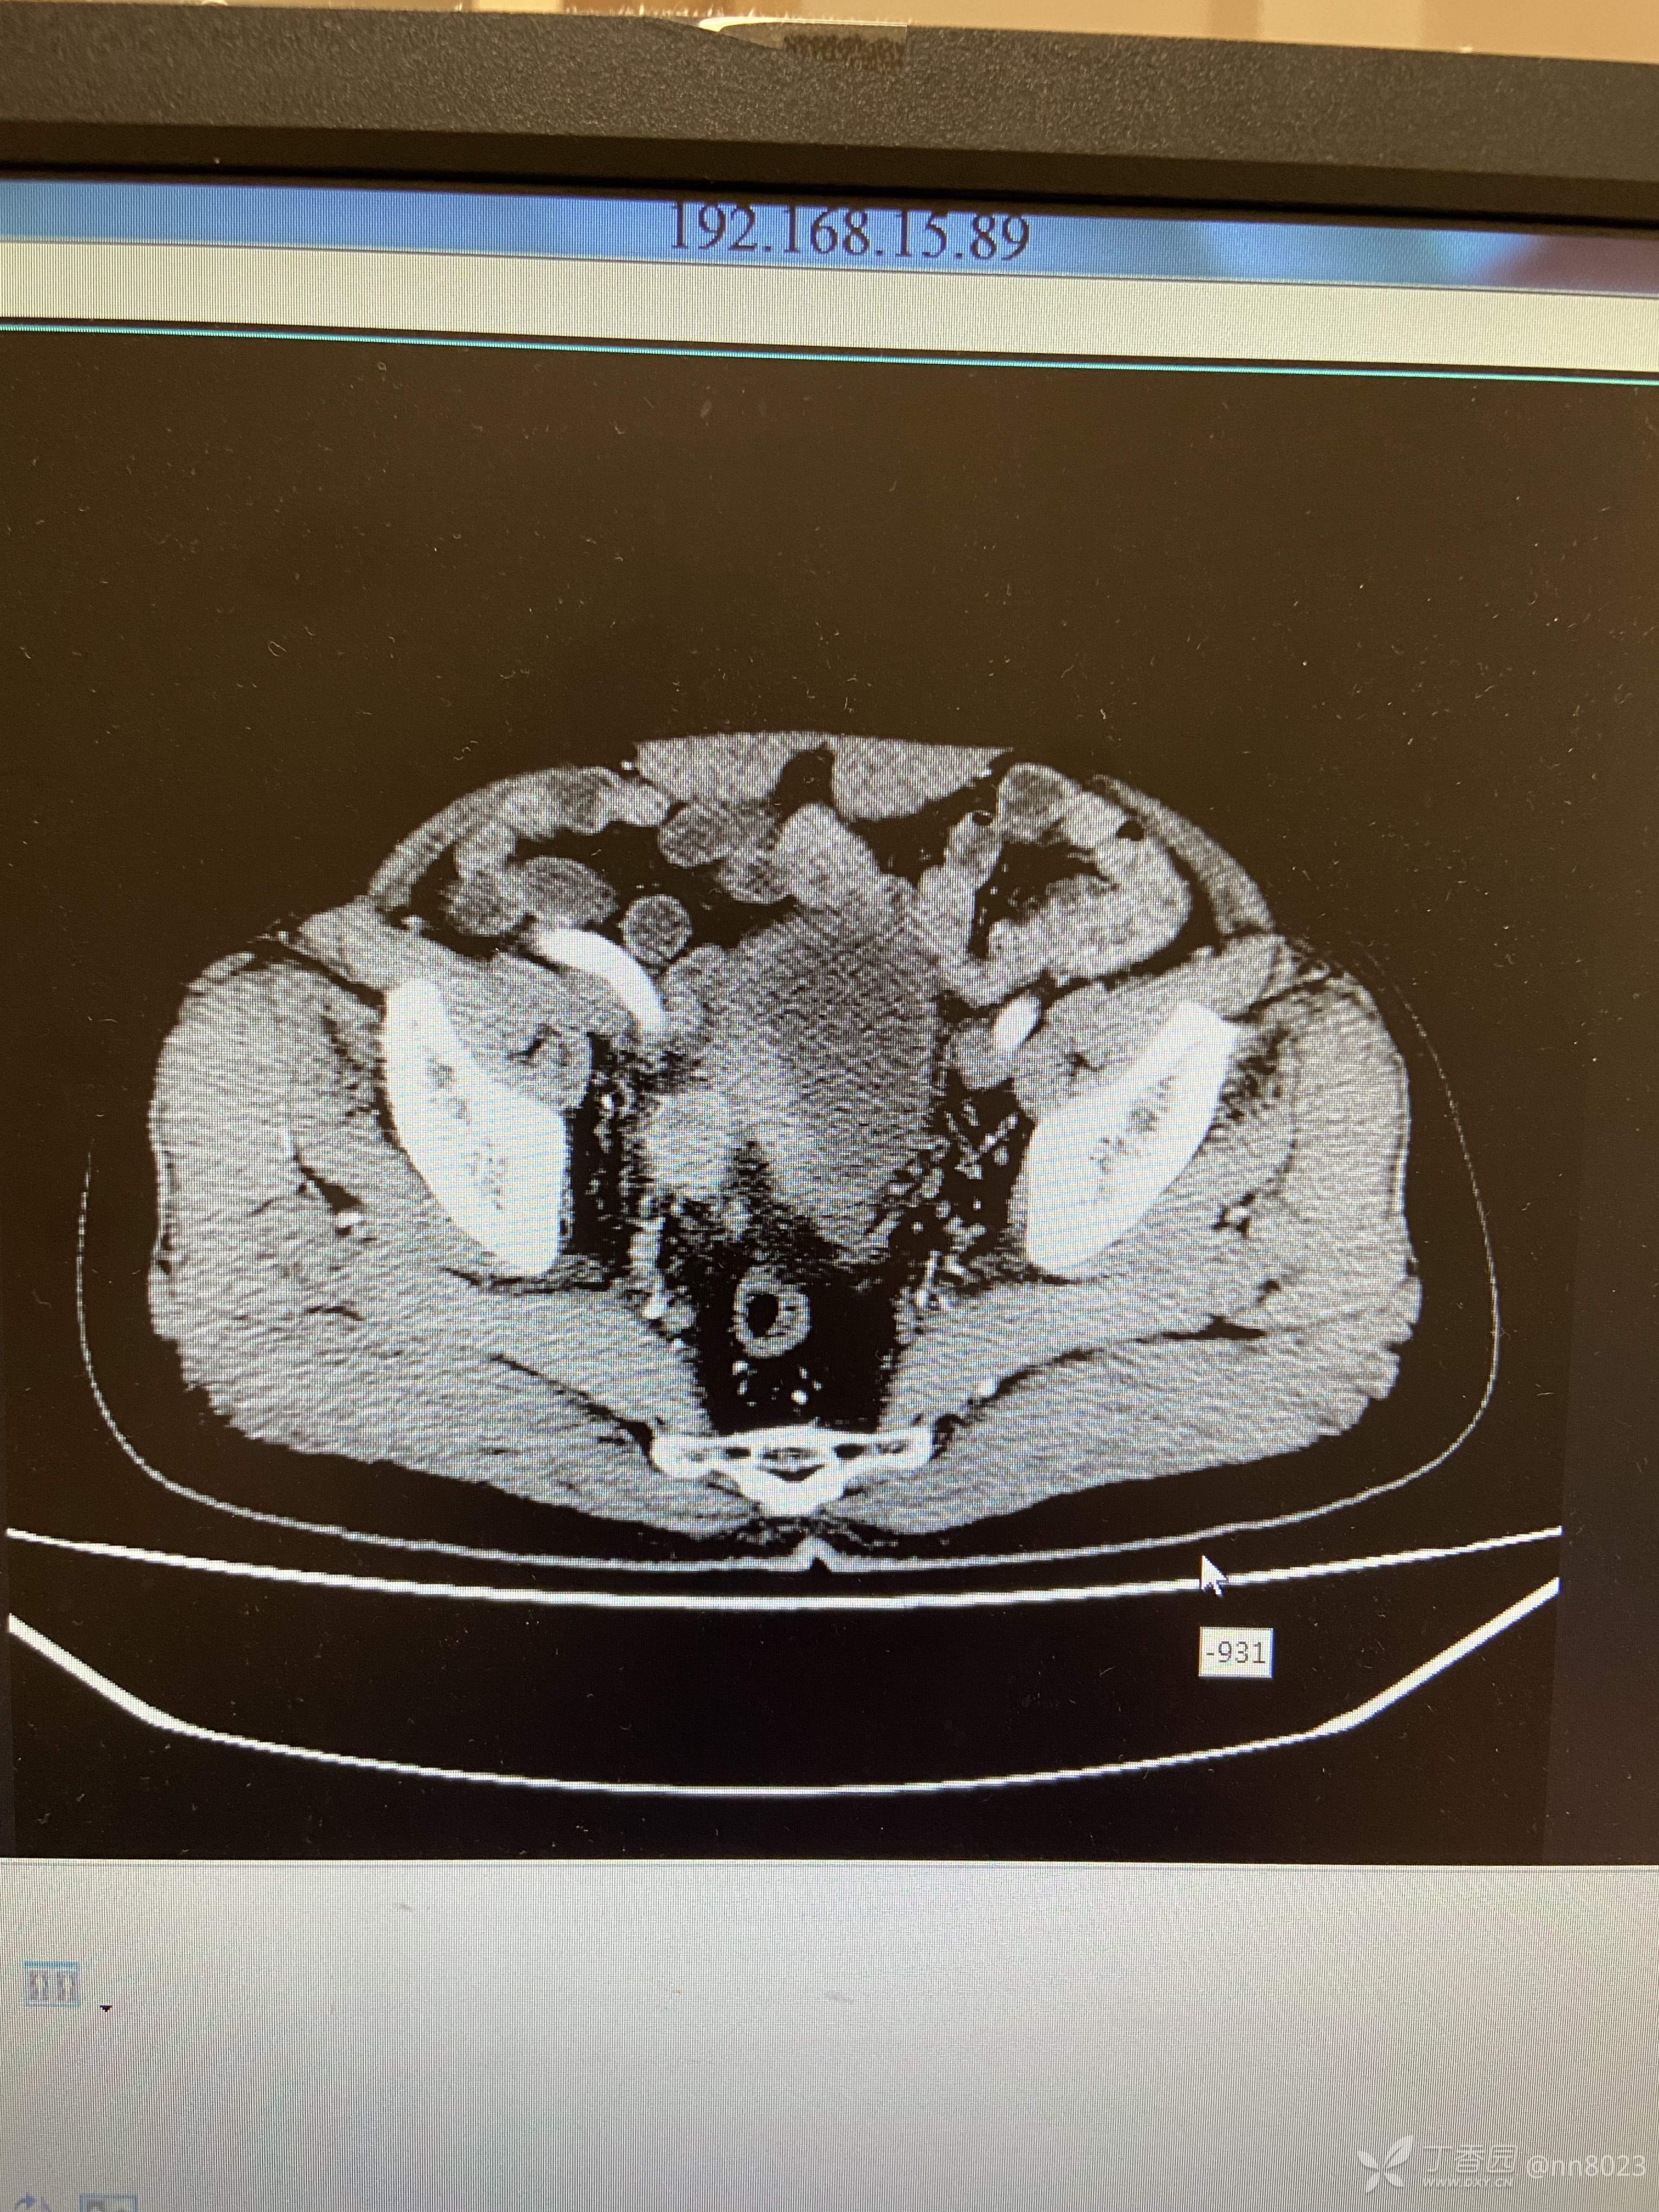

xiaospring +3 丁当66岁男性患者,因尿频尿痛于当地医院检查,彩超提示膀胱占位,完善增强CT